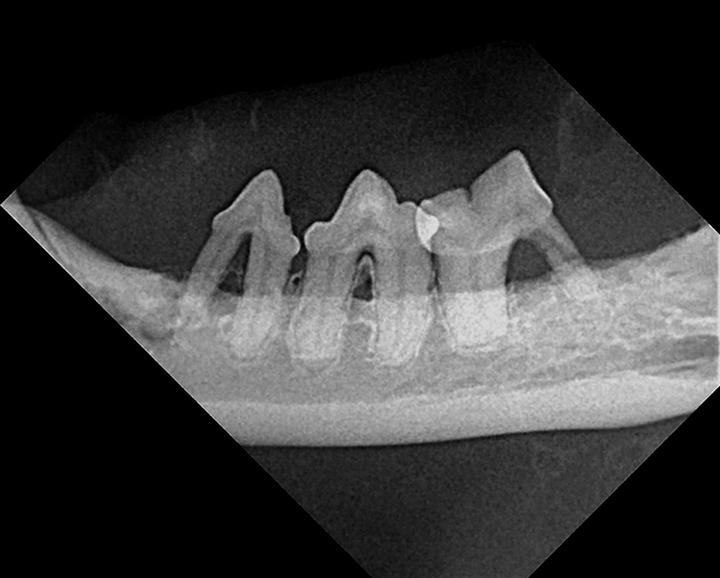

Close-up, lateral image of right cat maxilla.

FIGURE 1

Significant alveolar and labial/buccal mucositis, likely associated with advanced periodontal disease, in a 5-year-old neutered male domestic shorthair cat. Radiographs are recommended to evaluate for any changes (eg, tooth resorption).